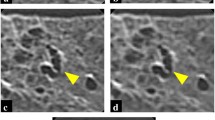

CT images of a cadaveric lung with pulmonary hemorrhage. AD-CT (area detector CT) image of a cadaveric lung with pulmonary hemorrhage (a). Zoomed CT images corresponding to a dashed rectangle in (a) are shown (b, c, and d). Intralobular reticular opacities can be detected more easily on AD-CT (b) than on U-HRCTSHR (c) and U-HRCTSHR-VOL (d). On the other hand, normal anatomical structures such as bronchi and vessels (arrow) can be seen more clearly on U-HRCTSHR (c) and U-HRCTSHR-VOL (d) than on AD-CT (b). U-HRCTSHR (c) and U-HRCTSHR-VOL (d) seem to also show normal anatomical structures such as small bronchi and vessels as low attenuation areas. While dark band artifacts (arrowheads) can be seen in (b), there are almost no dark band artifacts in (c and d).